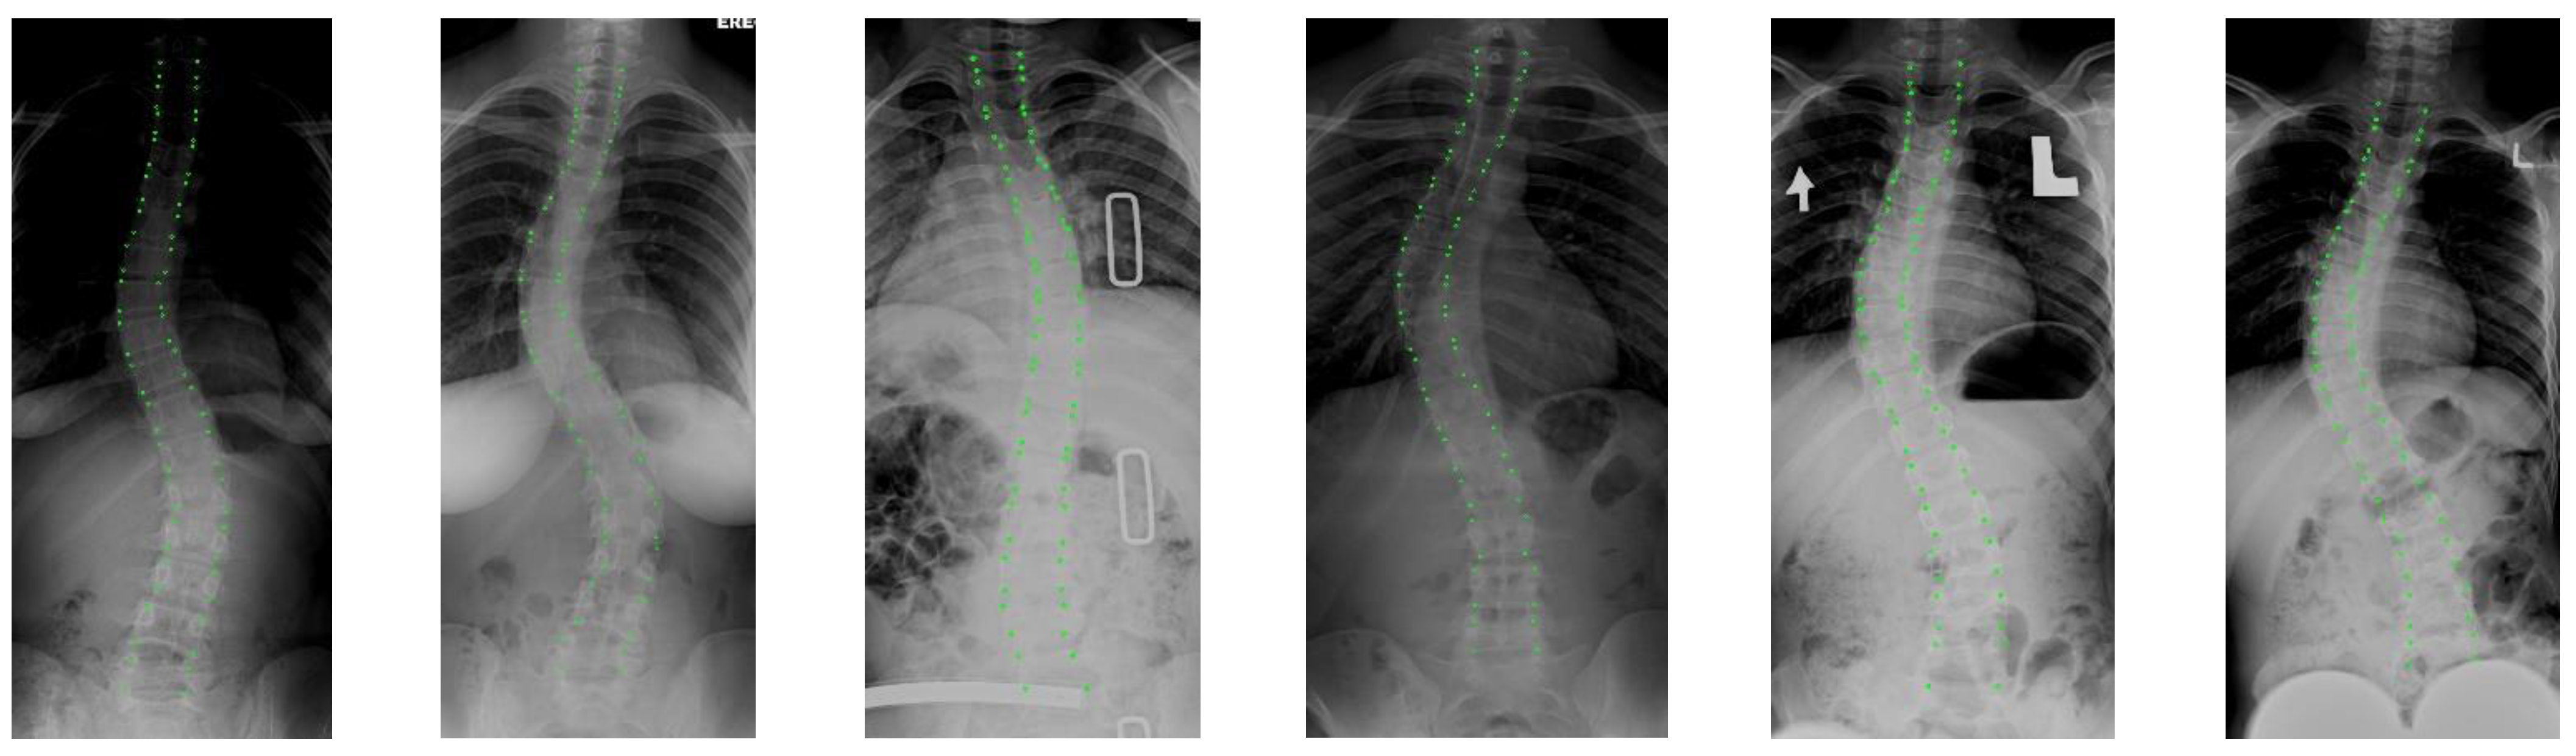

The quantitative experimental results of the compared methods are presented in Table 3, where ⊗ denotes that post-processing was not used for the segmentation results; √ denotes that post-processing was used; and + indicates the increase with the post processing used. To intuitively present the visual comparison, the segmentation effects of the different methods are shown in Figure 14, and some examples that illustrate the effects of post-processing are presented in Figure 15.

Figure 15.

The visual comparison of some examples to illustrate the effects of post-processing. GT: ground truth; Predict: without post-processing; OURS: the post-processing was used.

Third, by observing the results in Table 3 on whether post-processing was used, we note that the post-processing operation improved all methods under all indicators. This demonstrates that post-processing can effectively improve segmentation. Moreover, these improvements on quantitative segmentation indicators are not significant, as post-processing is primarily designed for subjective adhesions and speckles. From the visual comparison in Figure 15, each method can successfully remove some subjective segmentation errors, such as adhesions, speckles, and holes, which significantly contributes to the Lenke classification of scoliosis. In addition, it is worth noting that the post-processing strategy improved Unet++ and Unet more significantly than the other approaches from both objective indicator and subjective observation. This also causes Unet++ to be more advantageous in the Lenke classification of scoliosis. In the next section, we conduct more experiments to verify the performance of the segmentation networks involved in the proposed Lenke classification framework.

In summary, the Unet++ and Segmenter models achieved relatively superior segmentation results with post-processing. In addition, in the next sections, we further test the performance of these segmentation models that are incorporated into the proposed Lenke classification framework of scoliosis.